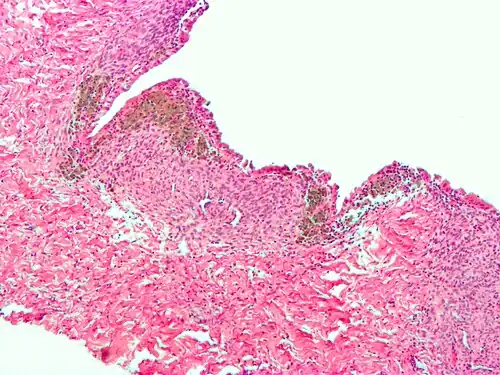

Histopathology

For a histopathological diagnosis, at least two of the following three criteria should be present:[121]

- Endometrial type stroma

- Endometrial epithelium with glands

- Evidence of chronic hemorrhage, mainly hemosiderin deposits

Immunohistochemistry is useful in diagnosing endometriosis as stromal cells have a peculiar surface antigen, CD10, thus allowing the pathologist go straight to a staining area and confirm the presence of stromal cells and sometimes glandular tissue is identified that was missed on routine H&E staining.[122]

Micrograph of the wall of an endometrioma. All features of endometriosis are present (endometrial glands, endometrial stroma and hemosiderin-laden macrophages).